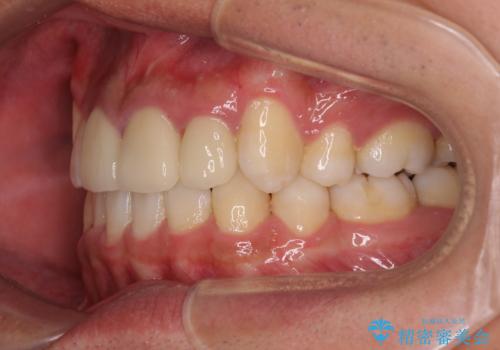

- 八重歯と上顎前歯の変色を気にして来院された患者様です。

上下ともに八重歯が顕著であったため、上下左右の第一小臼歯4本を抜歯し、ワイヤー装置での抜歯矯正を行うこととしました。

前歯の歯列が整ったことで、歯磨きが大変やりやすくなり、患者様には大変満足していただけました。